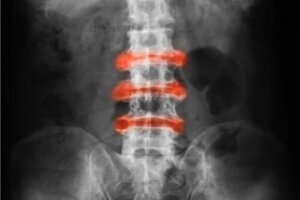

Dar ce este această boală? Este definită ca o artrită inflamatorie localizată în principal în articulațiile spatelui și ale pelvisului. Rigiditatea acută tinde să se amelioreze odată cu activitățile fizice.

- Spondiloartrita anchilozantă: artrită inflamatorie cu o incidență mai mare la nivelul coloanei vertebrale.

Cauze și simptome

Cauzele bolii nu au fost clarificate. Cu toate acestea, a fost detectată o tulburare în gena HLA-B27. Numărul bărbaților care suferă de spondilită anchilozantă este mult mai mare în raport cu cel al femeilor. În ceea ce privește simptomele, sunt evidente următoarele:

- Inflamație și durere la nivelul articulațiilor